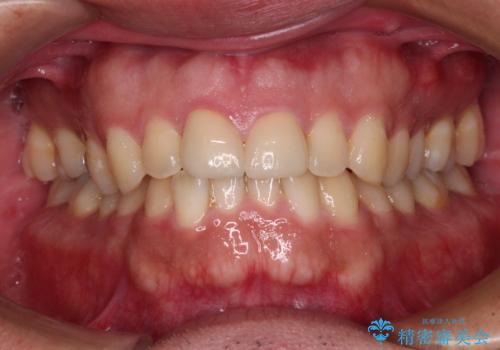

- 自転車で転んで前歯をぶつけたとのことで来院された患者様です。

事故後に受診した病院の歯科にて前歯2本の欠損した部分を修復されておりましたが、見た目が気になるとのことで、オールセラミッククラウンにて補綴治療を行うこととしました。

神経組織の状態を確認しましたが、片方は正常反応でしたが、他方は鈍い反応しかありませんでした。

速やかにオールセラミッククラウンにて補綴治療を行い、数ヶ月後に再度神経組織の状態を確認して、失活しているようであれば根管治療を行うこととしました。

しかしながら、補綴治療後間もなく再度自転車事故に遭い、追加1本の計3本を損傷する事態となりました。

再度損傷した3本は完全に失活した状態であったため、速やかに根管治療を行い、オールセラミッククラウンにて補綴治療を行うこととしました。